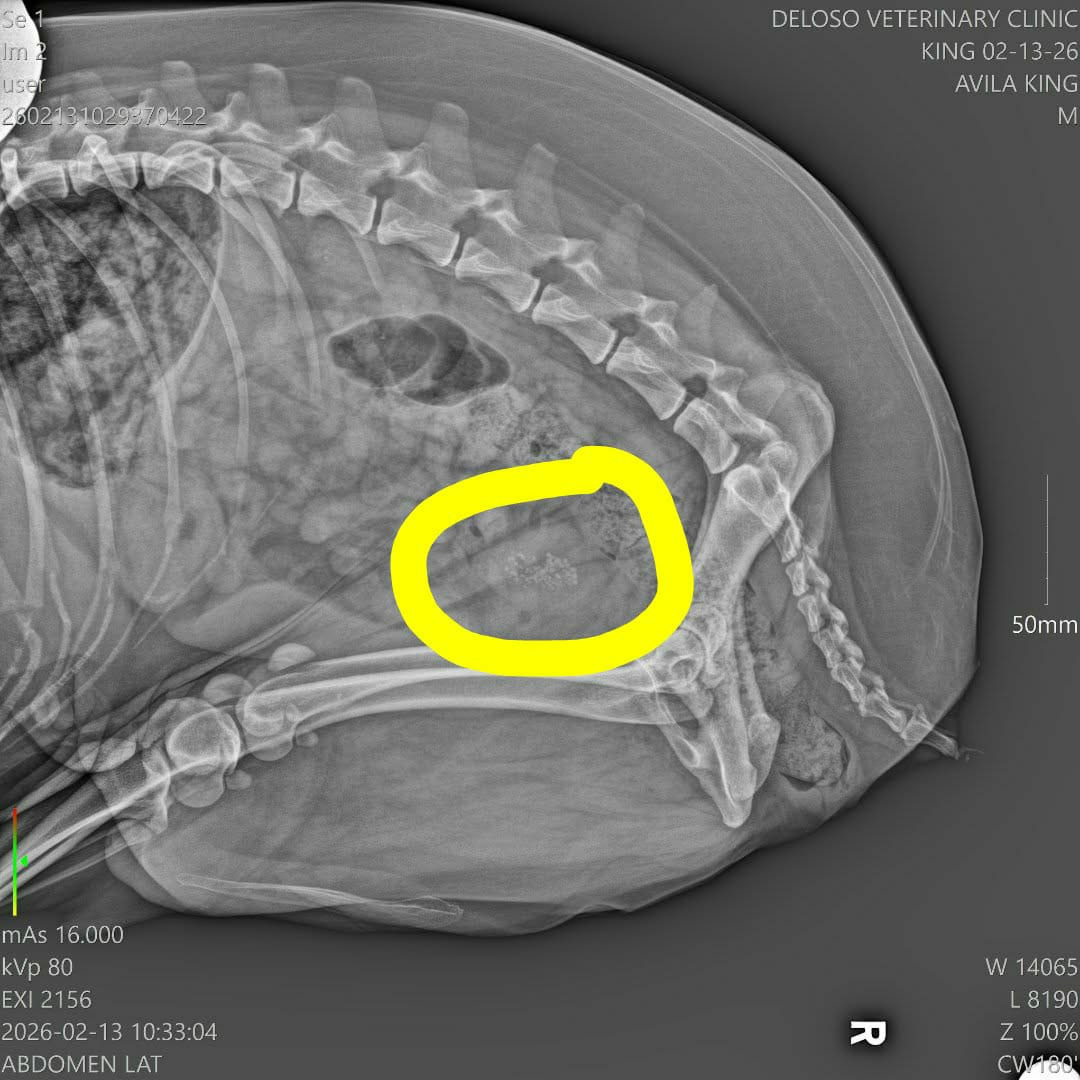

02.13.2026

I brought him to the vet for the third time. Unfortunately, the X-ray still showed the bladder stones. At this point, the only way to help him is through surgery to remove them.